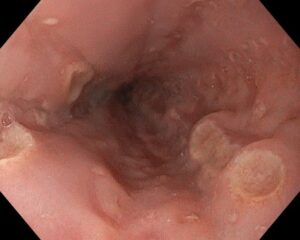

- Dificultad para tragar (disfagia): Es la sensación de que la comida se atasca. Incluso puedes tener atragantamientos. En gente joven, la esofagitis eosinofílica es una causa frecuente, así como las complicaciones del reflujo gastroesofágico. Otras causas más raras son los trastornos de la motilidad del esófago como la acalasia, las infecciones por Candida o por virus herpes. Y, por supuesto, siempre hay que tener en mente los tumores del esófago o, en pacientes ancianos, los problemas neurológicos de base.

- Reflujo ácido o acidez de estómago: Es muy frecuente en los países occidentales y está en relación con que cada vez tenemos más problemas de sobrepeso y obesidad. Si ya sabe que tiene problemas de reflujo, ojo con el consumo de tabaco o alcohol. Preste especial atención si el reflujo no mejora con omeprazol o sus derivados o si aparecen síntomas de alarma: pérdida de peso, anemia ferropénica o disfagia, entre otros. Si tiene reflujo refractario y ardor con sabor amargo, tendremos que pensar en el reflujo biliar. Como siempre, aprovechamos para recomendarle que no consuma tabaco ni alcohol. Sobre tabaco y cáncer puede aprender cosas curiosas aquí: Tabaco y cáncer

- Ictericia. Si la piel y / o los ojos se le ponen de color amarillo de repente, no tarde en consultar. Puede asociarse a la presencia de orina oscura (coluria), heces claras (acolia) o picores (prurito). Podemos estar hablando de un problema importante del hígado (una hepatitis aguda) o en las vías biliares. De estas últimas, las posibilidades más habituales como ejemplo de trastornos benignos y malignos, respectivamente, son las piedras en la salida de la vía biliar (coledocolitiasis) o un cáncer de páncreas.